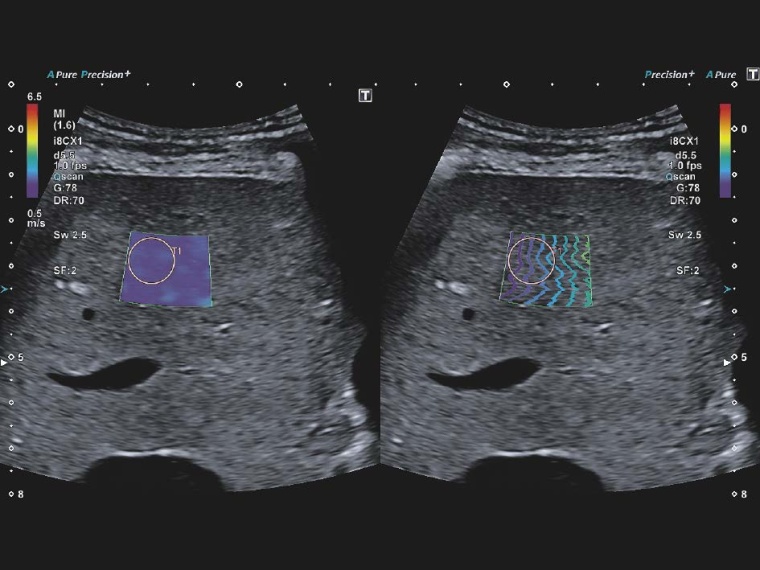

Das Liver Analysis Tool besteht aus drei Quantifizierungstools zur ultraschallbasierten Abbildung und quantitativen Beurteilung von relevanten Stadien diffuser Lebererkrankungen. Dies sind die 2-dimensionale Scherwellen-Elastographie, das Attenuation Imaging Tool und der Scherwellen Dispersion Mode.